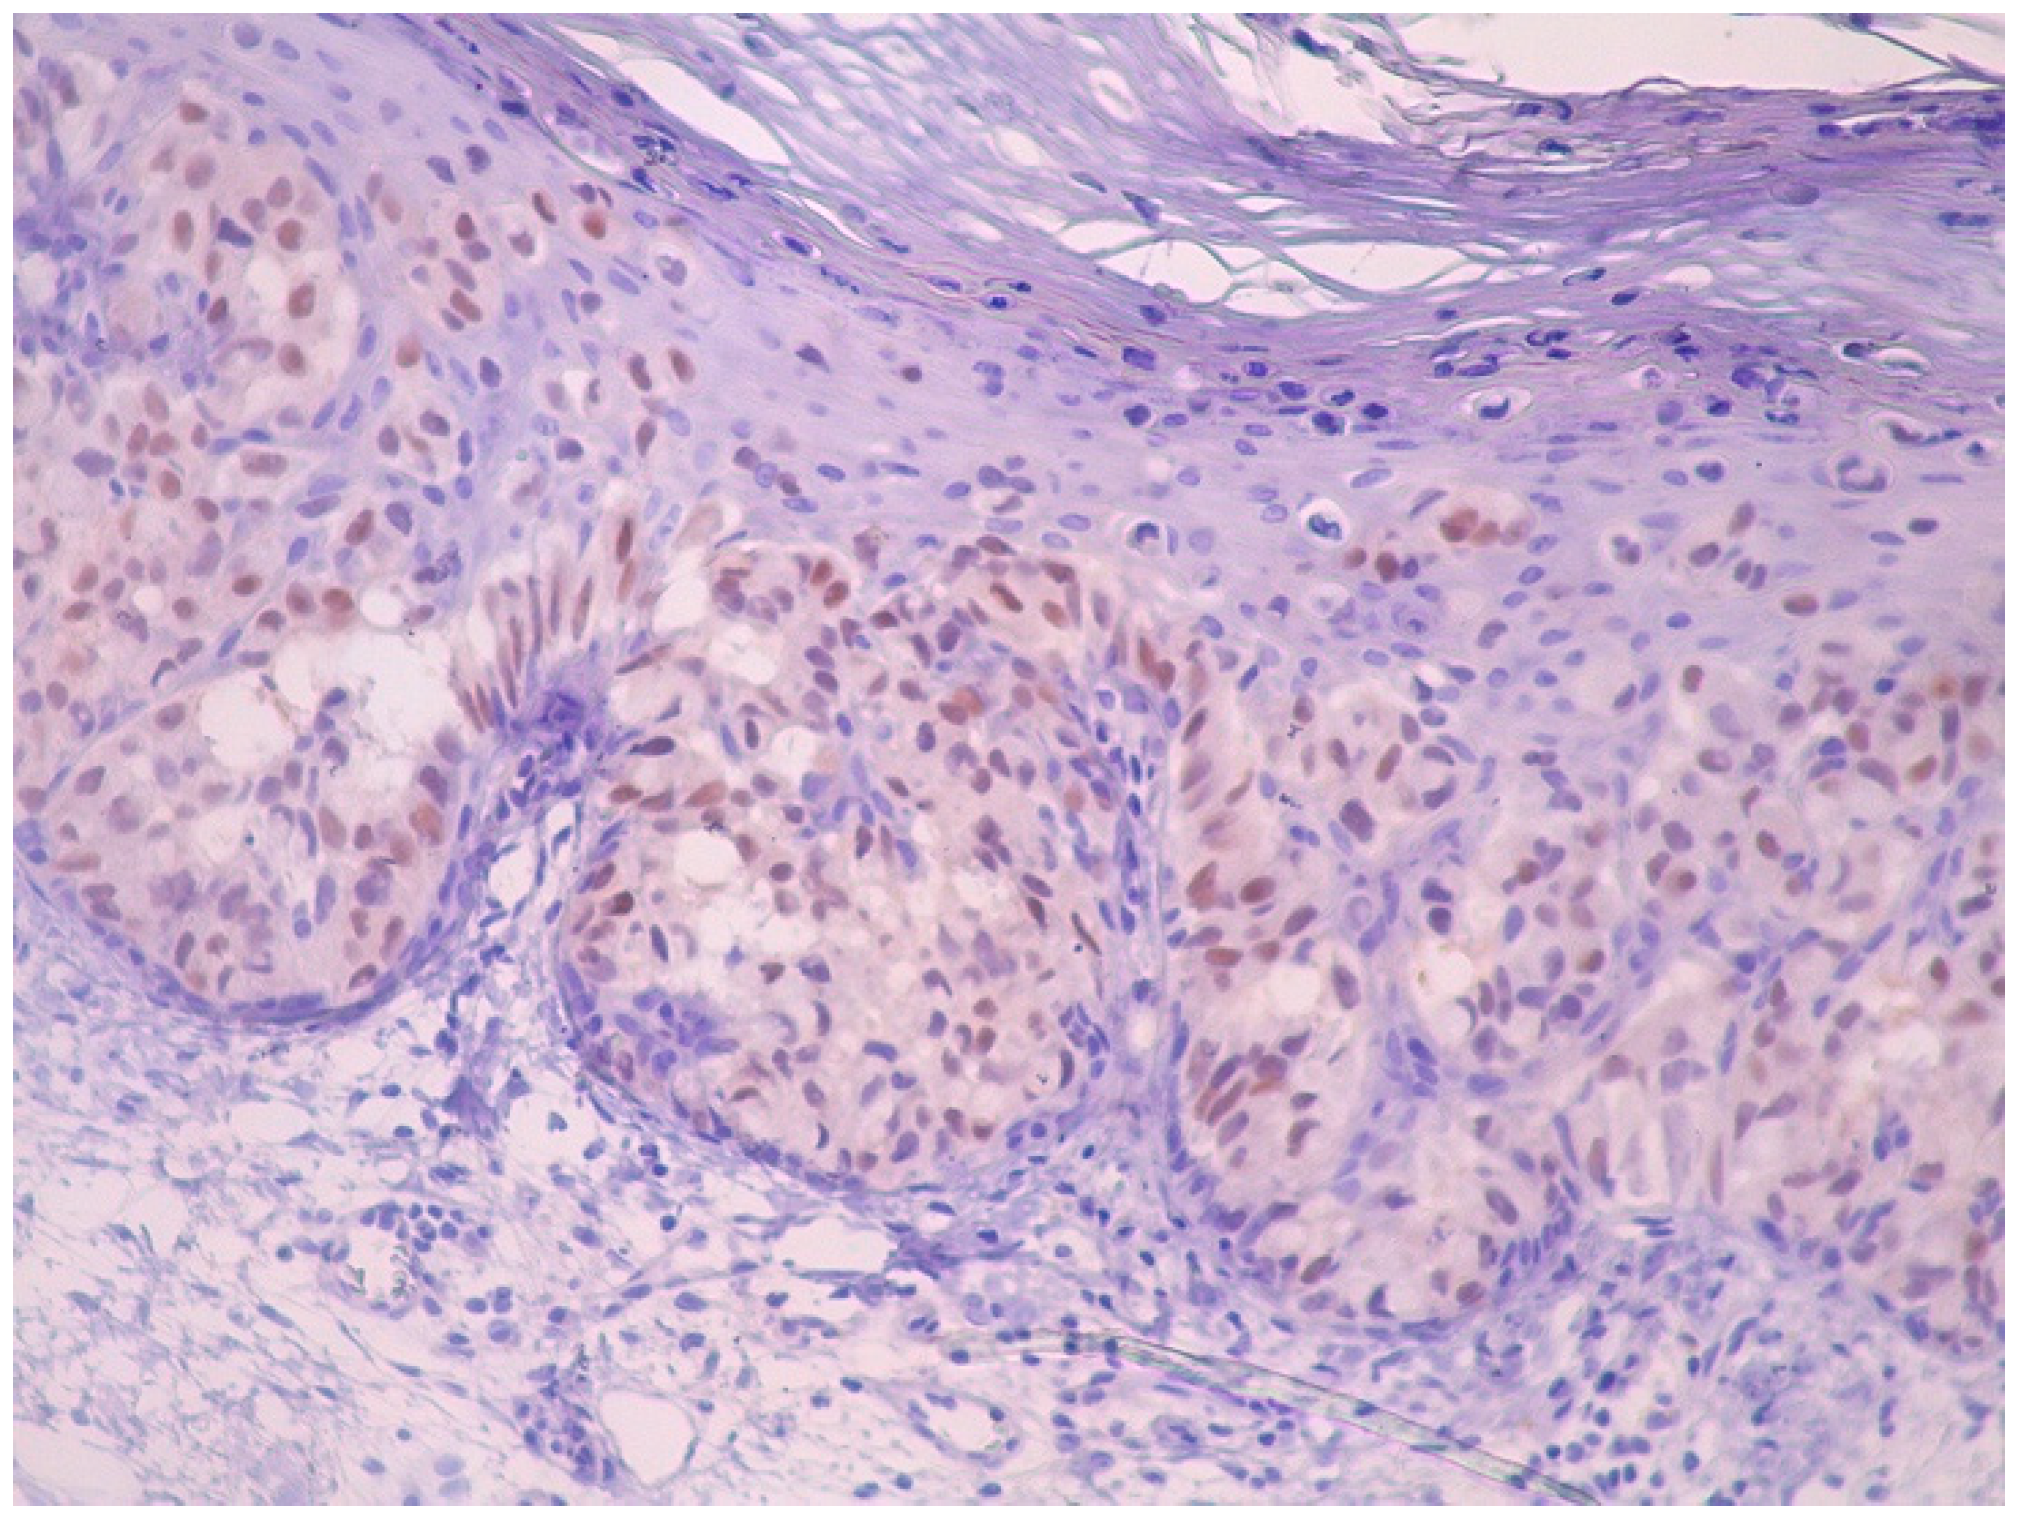

Histopathological examination of the biopsy specimens revealed skin covered by fibrino-leukocytic exudate with areas of epidermal ulceration. Medium-sized, atypical, discohesive tumor cells were observed in the epidermis and hair follicles, with pagetoid spread into the spinous layer. These atypical cells extended partially into the adnexal structures but did not infiltrate the dermis. The dermis showed moderate mixed perivascular inflammatory infiltrate and actinic elastosis (Figure 5).

Figure 5. Histopathological picture. Large cells with clear cytoplasm and atypical nuclei, arranged on their own or in nests in the epidermis (Paget cells), spread partially to the adnexa, but with no dermal infiltration (hematoxylin and eosin, original magnification, ×10 ×20).